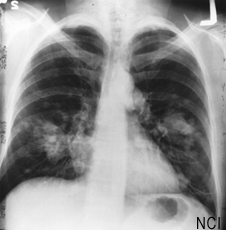

Hoy en día, los médicos a evaluar las primeras etapas de cáncer de pulmón por su apariencia tamaño, ubicación y microscópico. Esta información, conocida como puesta en escena, se utiliza para guiar el uso de un tratamiento adicional después de la cirugía. Si los médicos pueden medir con mayor precisión el pronóstico, más personas que podrían beneficiarse de una terapia adicional podría recibir inmediatamente después de la cirugía, antes de cualquier cáncer residual ha tenido la oportunidad de crecer.